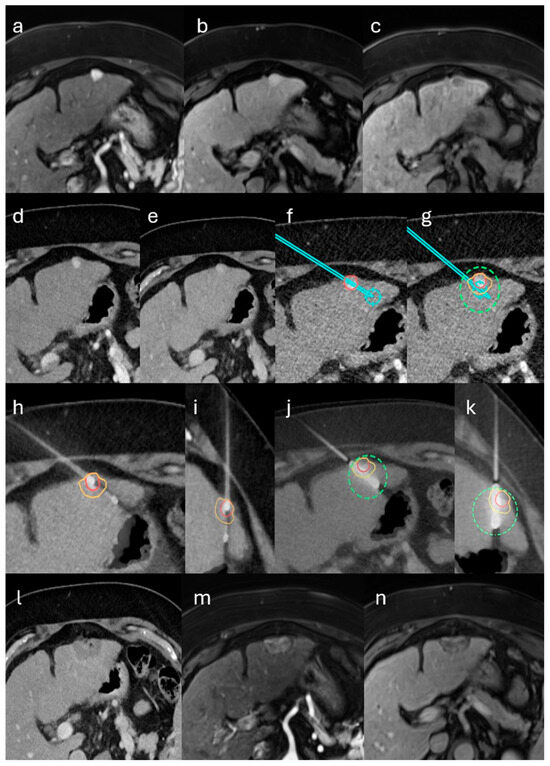

Combined Single-Session Stereotactic Biopsy and Microwave Ablation of Primary and Secondary Liver Tumors

by Liang Zhang, Anthony Ngu, Laura Sophia Kupke, Vinzenz Mayr, Quirin Strotzer, Moritz Brandenstein, Christian Stroszczynski and Ingo Einspieler

Biomedicines 2025, 13(12), 2865; https://doi.org/10.3390/biomedicines13122865 - 24 Nov 2025

Objective: To evaluate the safety, diagnostic yield, and ablation efficacy of a single-session workflow combining stereotactic percutaneous core-needle biopsy (CNB) immediately followed by microwave ablation (MWA) for liver tumors. Methods: We retrospectively reviewed consecutive patients (December 2021–May 2025) who underwent stereotactic CNB followed [...] Read more.

Objective: To evaluate the safety, diagnostic yield, and ablation efficacy of a single-session workflow combining stereotactic percutaneous core-needle biopsy (CNB) immediately followed by microwave ablation (MWA) for liver tumors. Methods: We retrospectively reviewed consecutive patients (December 2021–May 2025) who underwent stereotactic CNB followed by MWA in the same procedure. Primary endpoints were primary technique efficacy (PTE) and complications. Secondary endpoints were 6-month local tumor progression (LTP) and diagnostic yield. Six-month LTP was summarized using a Kaplan–Meier (KM) point estimate with Greenwood 95% CIs. Results: Thirty-three patients underwent single-session biopsy and ablation (33 biopsied; 41 lesions ablated). PTE was 95.1% (39/41); two residual tumors were successfully re-ablated. Six-month LTP was 3.6% (patient level; KM 95% CI 0.0–10.5%) and 2.8% (lesion level; KM 95% CI 0.0–8.2%). There was one major complication (3%, post-ablation abscess) and no minor complications. Adequate tissue was obtained in all biopsies; a definitive diagnosis was established in 88% (29/33): malignancy in 73% (24/33) and benignity in 15% (5/33); 12% (4/33) were nondiagnostic. In the hepatocellular carcinoma (HCC)-suspected subgroup (LI-RADS LR-3 to LR-5; n = 24), all LR-5 lesions were HCC (11/11). Among LR-4 lesions (n = 7), histology showed HCC in 1/7 (14%) and cholangiocarcinoma in 2/7 (29%); 4/7 (57%) were benign or nondiagnostic. Among LR-3 lesions (n = 6), 2/6 (33%) were HCC and 4/6 (67%) were benign or nondiagnostic. In the metastasis-suspected subgroup (n = 9), malignancy was confirmed in 8/9 (89%); 1/9 (11%) was nondiagnostic. Conclusions: Single-session stereotactic CNB followed by MWA is feasible and safe, yields diagnostically useful tissue, and achieves high ablation efficacy. Full article

(This article belongs to the Special Issue State-of-the-Art Hepatic and Gastrointestinal Diseases in Germany)